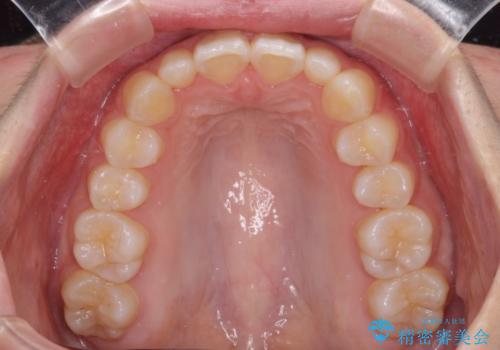

前歯のデコボコを治したい インビザラインによる矯正治療

- 前歯のデコボコ気になるとのことで来院された患者様です。

上下顎ともに歯列全体の後方移動とIPR(歯と歯の間を削る)によってデコボコが解消するように設計し、インビザラインにより治療を行うこととしました。

上顎左右前歯に矮小歯があるため、上顎の奥歯は下顎に対して相対的に前方に位置することになりました。

それでも奥歯の咬みにくさはなく、患者様には大変満足していただきました。